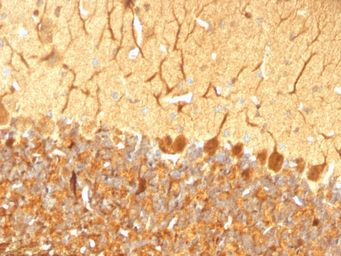

IHC-P analysis of rat cerebellum tissue using GTX34970 PGP9.5 antibody [SPM574].